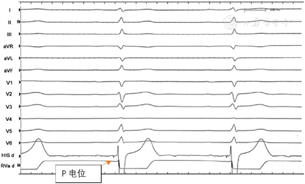

血常规:血红蛋白147 g/L,白细胞计数9.37×109/L,血小板计数227×109/L;血肌酐98 μmol/L,血清尿素氮6.4 mmol/L,尿酸321 μmol/L;NT-proBNP 3335 pg/ml。肝功能:总胆红素17.7 U/L,丙氨酸氨基转移酶16 U/L,天冬氨酸氨基转移酶18 U/L。甲状腺功能:未见异常。自身免疫抗体:均阴性。心电图:窦性心律,完全性左束支传导阻滞,QRS波时程160 ms(图1)。

手术过程:常规采用左侧腋静脉入路,J型导丝引导下送入C315鞘(美国美敦力公司)至右心房,经鞘管送入美敦力3830导线至房室沟和三尖瓣环处希氏束的位置,先进行希氏束标测,确定希氏束位置,在右前斜位30°,将远端希氏束部位与心尖连线方向的1~1.5 cm处的右心室面作为初始部位,逆时针旋转鞘管,保持导线头端垂直于室间隔,寻找起搏时V1导联呈"W"形,顿挫在QRS底部的右心室间隔位点。定位后快速旋转导线拧入电极。起搏图形由左束支阻滞形态逐渐变为右束支阻滞形态。旋入过程中动态监测3830导线单极阻抗、单极起搏图形以及测量高电压(5V)、低电压(阈值电压)起搏状态下的左心室达峰时间。左束支夺获的判断标准如下:(1)起搏形态为右束支传导阻滞(right bundle branch block,RBBB)形态,起始陡峭;(2)记录左束支电位(P电位)(图2);(3)观察到选择性左束支起搏图形(S-LBBP)(图3)。本病例表现为:当输出电压为5V@0.4ms时,腔内心电图呈现非选择性左束支起搏图形(NS-LBBP)。即起搏信号与QRS波之间无等电位线,心电图V1导联呈QR型;当输出电压降低为1V@0.4ms时,腔内心电图呈现S-LBBP。即起搏信号与QRS波之间存在等电位线或间隙,心电图V1导联呈M型,R波宽且有切迹;(4)随着电压增高,左室达峰时间骤然缩短,且输出继续增高时,达峰时间保持不变;(5)起搏纠正阻滞,恢复前传电位顺序,证实直接传导束夺获。记录左室达峰时间(stimulus to peak LV activation time,Sti-LVAT)为75 ms;R波幅度:12 mV,阈值:1.0 V,阻抗:580欧姆。撤去C315鞘后再测试参数,满意后连接DTBA2D1脉冲发生器。术后复查心电图:QRS波时限明显缩短(120 ms)(图4)。